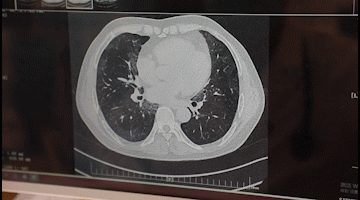

李先生入院后,胸科醫(yī)院吳昌歸院長(zhǎng)、朱運(yùn)奎副院長(zhǎng)組織科室進(jìn)行了深入討論,為其做了詳細(xì)檢查。醫(yī)生先做了導(dǎo)航下氣管鏡冰凍活檢,但病理未獲明確診斷。根據(jù)胸部CT特征、病變過程治療的反應(yīng),醫(yī)生懷疑是罕見的肺泡蛋白沉積癥。再經(jīng)肺泡灌洗液分析、PAS染色及診斷性分段灌洗后復(fù)查,證明醫(yī)生診斷正確。李先生確診為“肺泡蛋白沉積癥(繼發(fā)性)、肺炎、1型呼吸衰竭,并伴有慢性乙肝、高血脂癥等。

經(jīng)過4次的治療,李先生沉著于肺泡內(nèi)蛋白樣物質(zhì)漸漸消失,灌洗液為透明色。復(fù)查胸部CT肺部病變明顯吸收。經(jīng)再次灌洗治療后病變完全吸收,恢復(fù)健康。